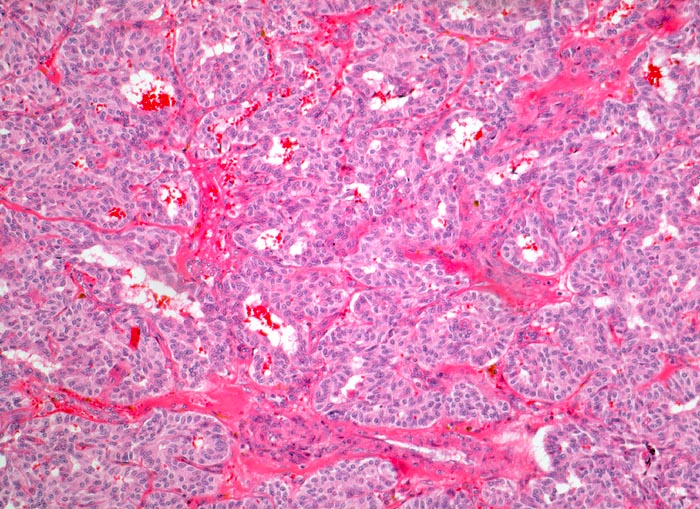

medulläres Schilddrüsenkarzinom

Aus polygonalen und spindeligen Tumorzellen aufgebauter teils trabekulärer, teils alveolärer Tumor. Dazwischen schmale Bindegewebssepten.

Graubrauner teils unscharf begrenzter Knoten in der Schilddrüse. Tumorzellen CEA und Calcitonin positiv.

jeder morphologisch ungewöhnlich aussehende Schilddrüsentumor sollte immunhistochemisch untersucht werden mit Antikörpern gegen Calcitonin, CEA und Thyreoglobulin.

100